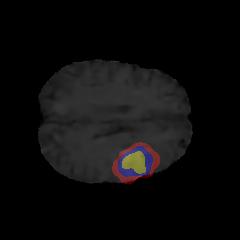

Brain tumor segmentation. Segmenting tumors in brain is challenging due to the high variance in appearance and shape of the tumors [28]. We use a subset of the 2017 Brain Tumour Image Segmentation (BraTS) dataset [29, 26]. It contains multi-parametric 3D MRI scans. The segmentation masks include (possibly overlapping) three classes of tumor. The 3D scans are split into 2D image slices, and only images that contain at least one tumor class are retained. Figure 7 shows three MSGNet generated samples as well as the corresponding masks. Since MSGNet adheres to the underlying relationships between various classes, we see that the generated images and the masks for different tumor classes are in line with the images and masks from the training set. In general, MSGNet rarely generated erroneous samples; we found roughly one sample per 3000 generations that could be rejected. Similar to the malaria experiment, we observed an improvement of 3.1% () in -score on the validation set.

A subset of the BrATS dataset was used. We used the images accompanied by segmentation layouts from the FLAIR and T1Gd modes. The segmentation layouts showed the sub-regions for three different classes: GD-enhancing tumor, the peritumoral edema, and the necrotic and non-enhancing tumor core. The brain and the background were treated as an additional class. We refer to [32] for further details. For the two modes, the background has been modelled using two different classes. We only considered half of the 155 slices, i.e., we took only the even-numbered slices and out of those we discarded the slices that did not include one of the previously mentioned tumor-classes in order to create a more balanced dataset. This resulted in 20,000 images that were further augmented with 6,000 MSGNet generated images. Example generations of the masks as well as the images are shown in Figure 12.